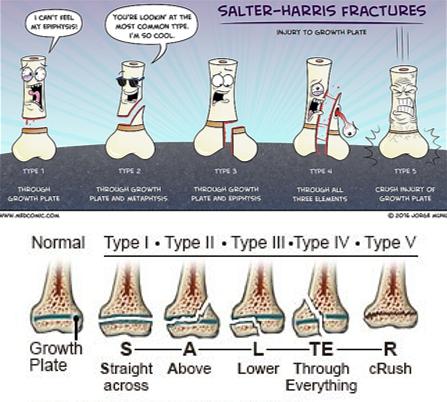

Salter-Harris Fractures

The Salter-Harris Classification system is used to describe fractures involving the epiphyseal growth plate.

These injuries have a higher likelihood of healing difficulties.

The most common concern is:

Growth arrest with the potential for deformity and limb length discrepancy.

Salter-Harris I and II fractures can be treated with closed reduction, casting, or splinting.

Salter-Harris III, IV and V will require surgery—open reduction.

Salter-Harris V fracture diagnosis may be delayed unless there is a high degree of clinical suspicion, and often the diagnosis is not made at the initial presentation.

May see in a follow-up examination as the patient starts to have some healing.